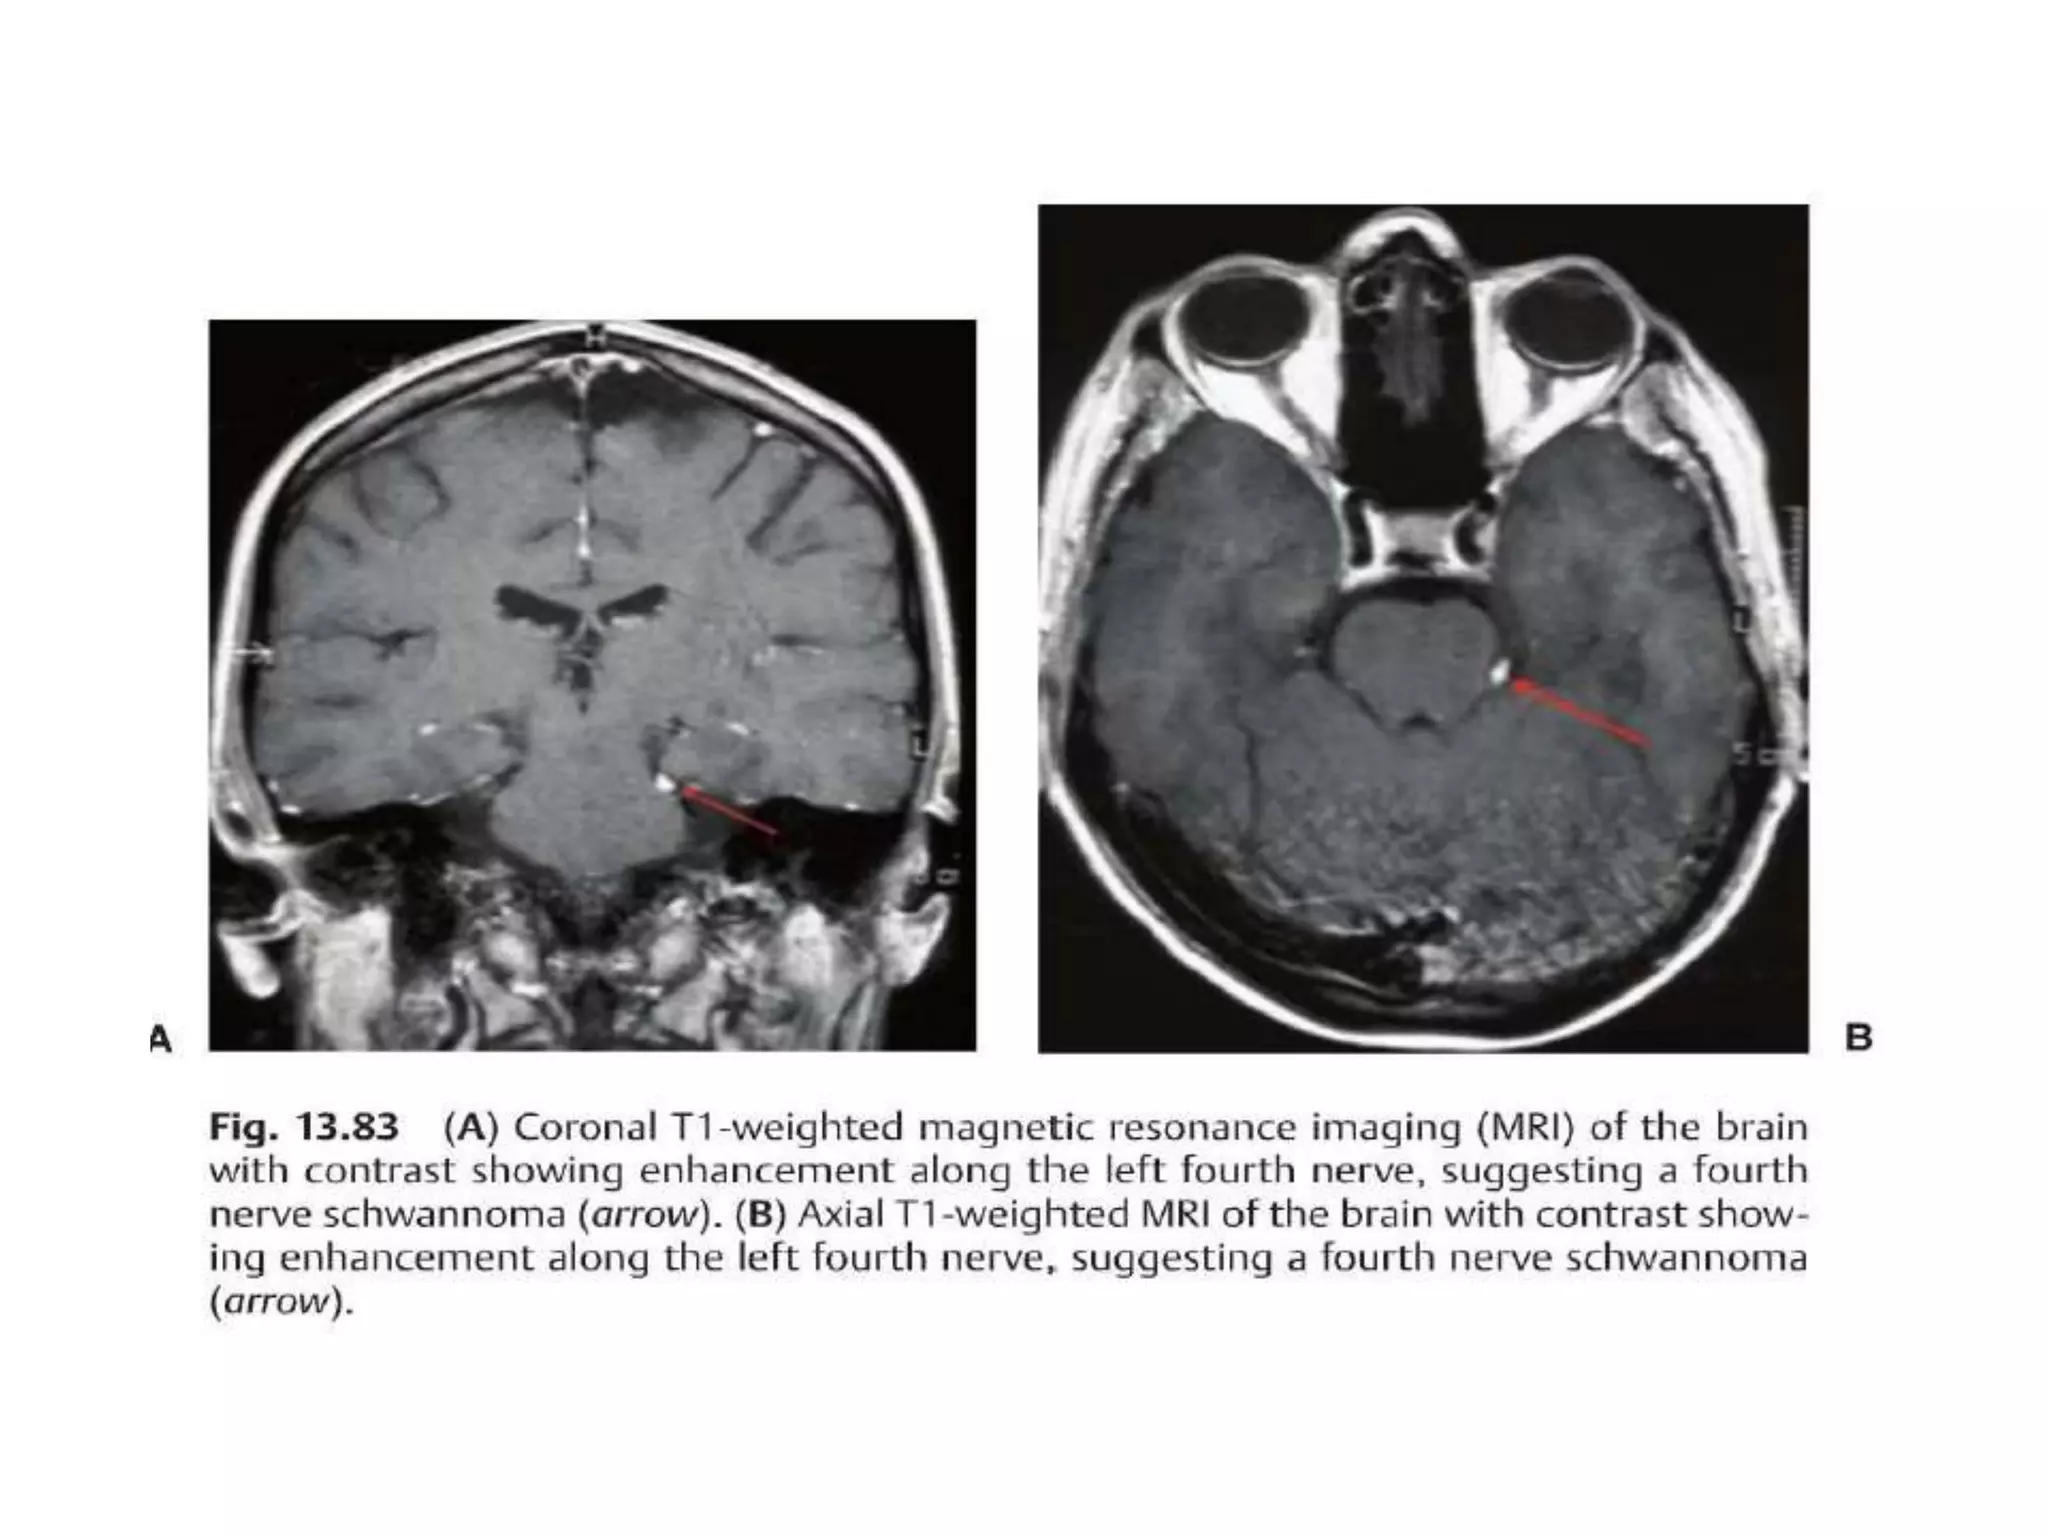

4th n. anatomy

• Nucleus(periaqueductal gray matter)->Cross over (midbrain)-

>subarachnoid space->Between cerebellar a. and post. cerebral a.-

>cavernous sinus(above V1)->sup. orbital fissure, annulus of Zinn-

>Sup. Oblique m.

4th n. palsy common cause

Evaluatioin

• Trauma? No further Work up

• Pt (>50 yrs)

– CBC, BC, CRP, ESR, glucose, lipid

• Brain MRI

4th n. anatomy •Nucleus(periaqueductal gray matter)->Cross over (midbrain)- >subarachnoid space->Between cerebellar a. and post. cerebral a.- >cavernous sinus(above V1)->sup. orbital fissure, annulus of Zinn- >Sup. Oblique m.

4th n. palsycommon cause

Evaluatioin • Trauma? Nofurther Work up • Pt (>50 yrs) – CBC, BC, CRP, ESR, glucose, lipid • Brain MRI